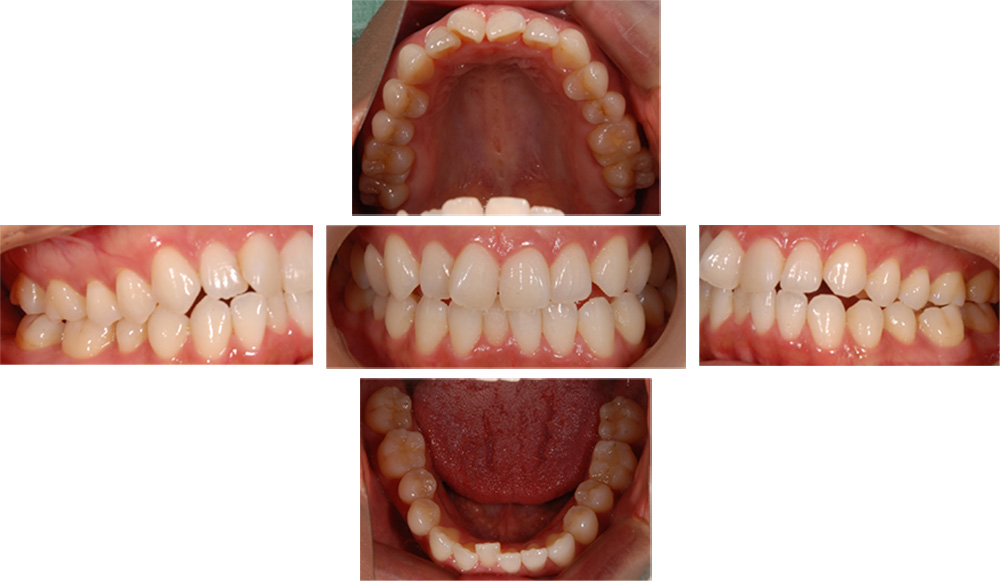

| 治療回数 | 36回 |

|---|---|

| 年齢・性別 | 30代 女性 |

| 治療期間 | 1年10ヶ月 |

| 治療費用 | 990,000円(税込) |

| 調整費 | 6,600円×来院毎(税込) ※2年目から |